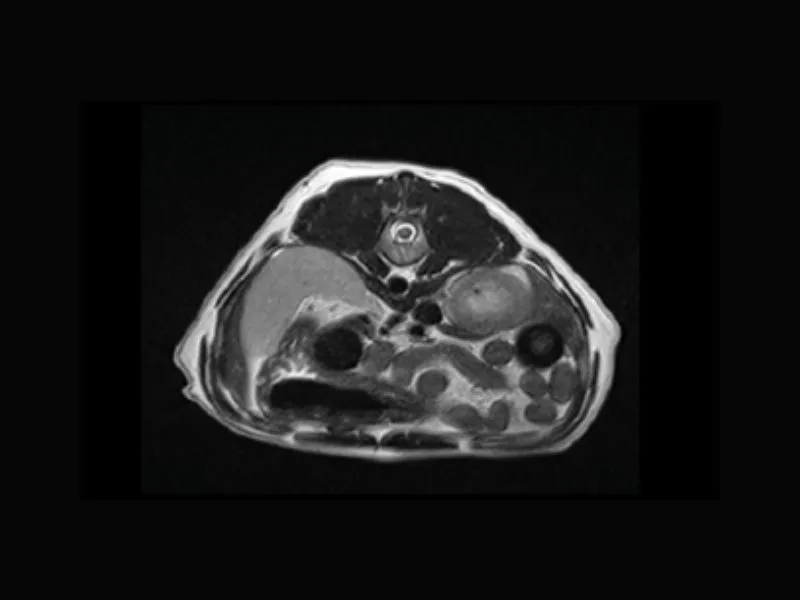

Supreme vet-mr – Transverse T2W with “Propeller” technique